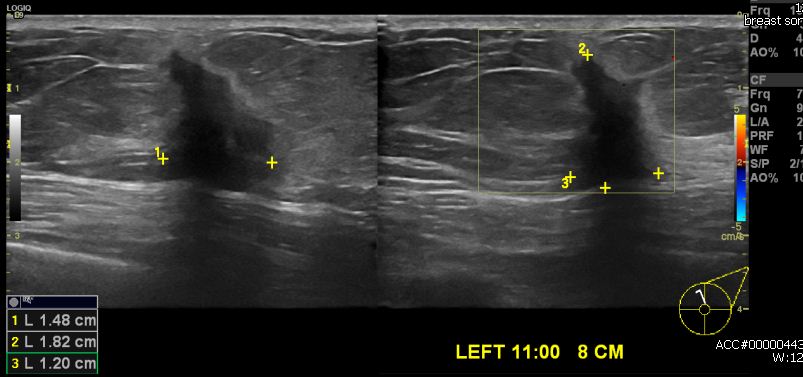

상기환자 건강검진상 이상 소견으로 내원하신 60대 여성분으로 좌측 11시 방향에서 8cm

떨어진 거리의 혹 조직검사 시행하여 좌측 침윤성 유관암 진단 되었습니다.